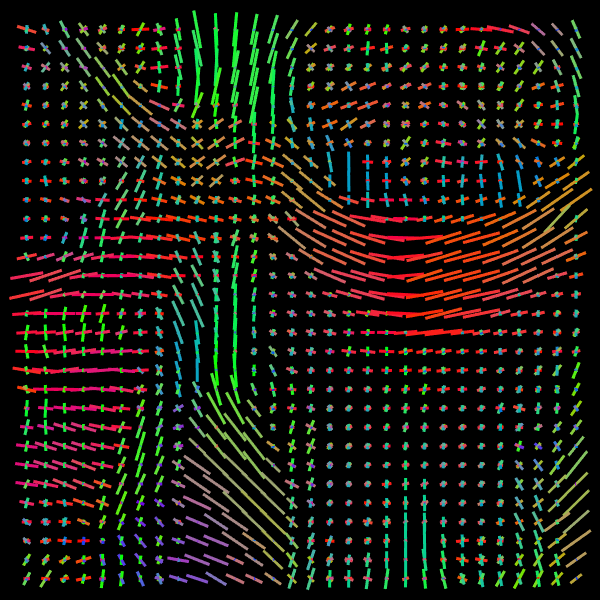

Training stage. We compare the results of the proposed Voxel (VOX) and Neighborhood (NBH) models with two of the SOTA methods which tackle the same task: Diffusion Basis Functions (NNLS) proposed by Ramirez-Manzanares et al. (2007)) and Constrained Spherical Deconvolution (CSD) proposed by Tournier et al. (2007). There are many options to compare distributions, a common comparisson procedure used in this context is to detect peaks and compute the angular error between the real peaks and the estimated ones. However, to compare modes in not a standard procedure for comparing distributions. Among them two notable options are Kullback-Leibler (KL) Divergence and the Wasserstein Distance (also know as the Earth Mover Distance, EMD). Despite its computational cost, EMD has shown to represents more precisely the distribution distance (Levina and Bickel, 2001; Aranda et al., 2011; Arjovsky et al., 2017). EMD represents the minimum cost of transforming a peak distribution into another, weighting by angle. We create a synthetic dataset with gradient table of the Stanford HARDI dataset (Rokem et al., 2015), the eigenvalues of a Diffusion Tensor model fitted to the corpus callosum region, and the SNR computed in such a data (Descoteaux et al., 2011). The estimated SNR depends on image region: most of the measures laid into [20,24]2024[20,24], so we randomly generate data selecting the SNR into [20,30]2030[20,30]. Figure 5 depicts the error for each analyzed model. The vertical axis corresponds to the angle (θ1subscript𝜃1\theta_{1}) between the first PDD and the second one. Meanwhile, the horizontal axis shows the angle between the third PDD and the plane formed by the first two PDDs. The dynamic range of the error maps shows a better performance of the proposed models. We select some predictions for a visual inspection (qualitatively comparison). For illustration purposes, we choose one between the top–101010 and one of the bottom–101010 according to its EMD values for the studied models: VOX, NBH, NNLS, and CSD. The results are presented in Figure 6. The first two columns correspond to the best predictions: the first column shows the target and the second column shows the prediction. The third and fourth columns follow the same order but for the worst predictions. Arrows illustrate the generated PDDs (ground truth). According to the α𝛼\alpha value: blue, orange, and green were used for the first, second, and third PDD, respectively.

Refer to caption

Figure 6: Predicted voxels with lowest (first two columns) and highest error (last two columns).